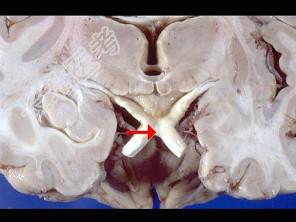

- 单项选择题如图箭头所示为视觉系统哪个部位 ( )

A、视束

B、视交叉

C、视不变

D、视乳头

E、视神经